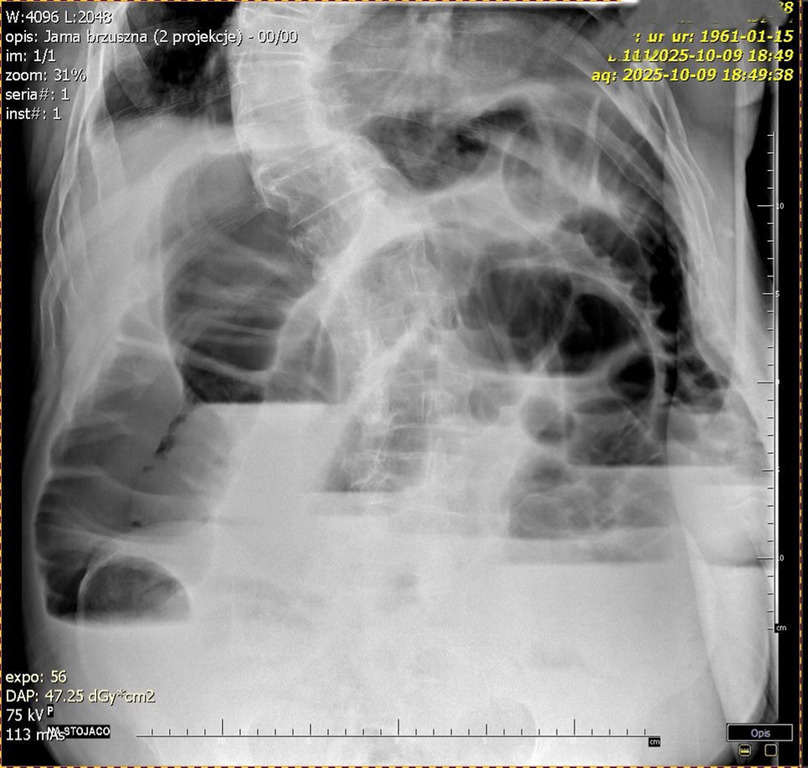

Diagnostyka: Wykonuje się przeglądowe zdjęcie RTG jamy brzusznej w celu potwierdzenia niedrożności (ryc. 1 i 2) i/lub tomografię komputerową (TK) ujawniającą rozdęte pętle jelit powyżej guza (ryc. 3).